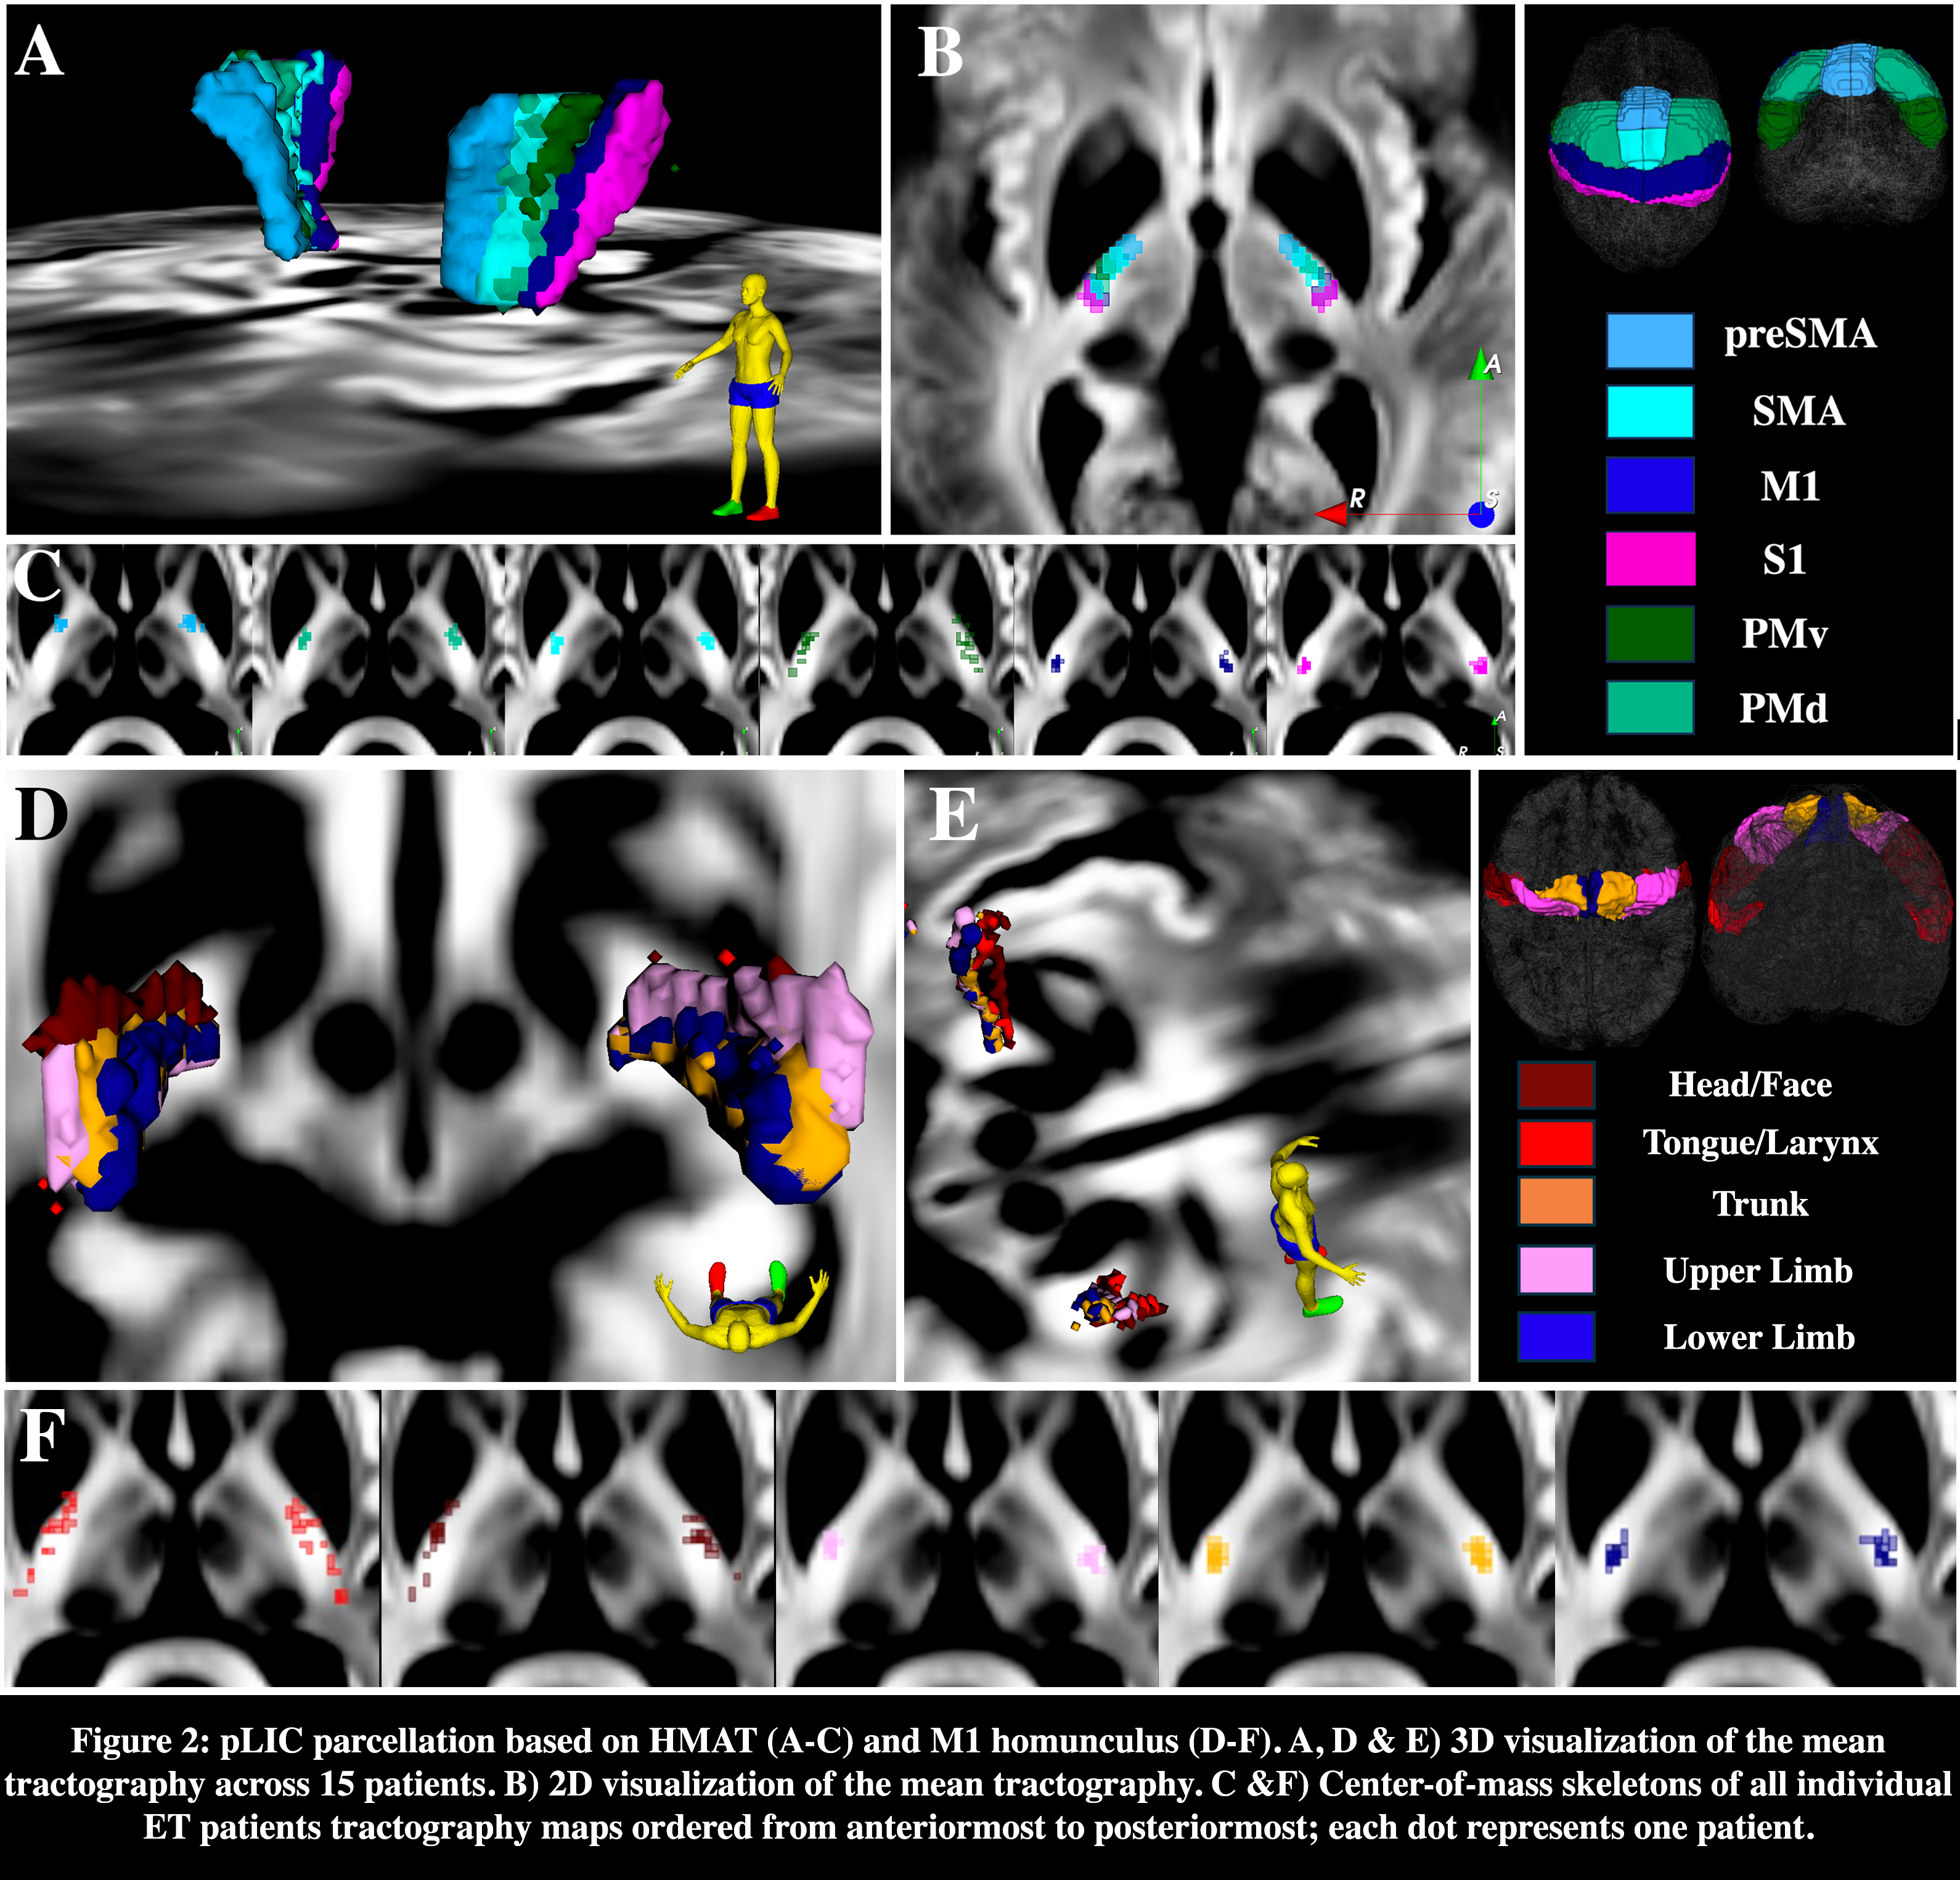

Results: PICS was consistently identified across multiple MRI sequences, but more easily idendified in DiMANI sequences in all patients (Fig.1). Tractography analyses identified PICS to correlate with the distribution of motor fibers from the internal capsule (Fig.2A-C). For the M1 homunculus, two somatotopic clusters were observed: one including mostly trunk, lower and upper limbs; and another, more anteriorly, with head/face clustering with tongue/larynx (Fig.2D-F). Intra-operative stimulation at two different depths resulted in pLIC-specific side effect in the tongue/face. At those depths, measurements showed closer proximity of the DBS electrode to M1 clusters of head/face and tongue/larynx, validating the imaging findings (Fig.3).

Fig.2